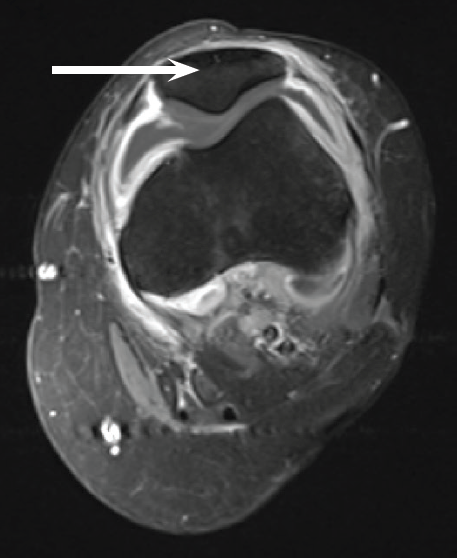

An 18-year-old young adult presented with a 1-week history of progressive left knee pain and swelling.

07/21/2015